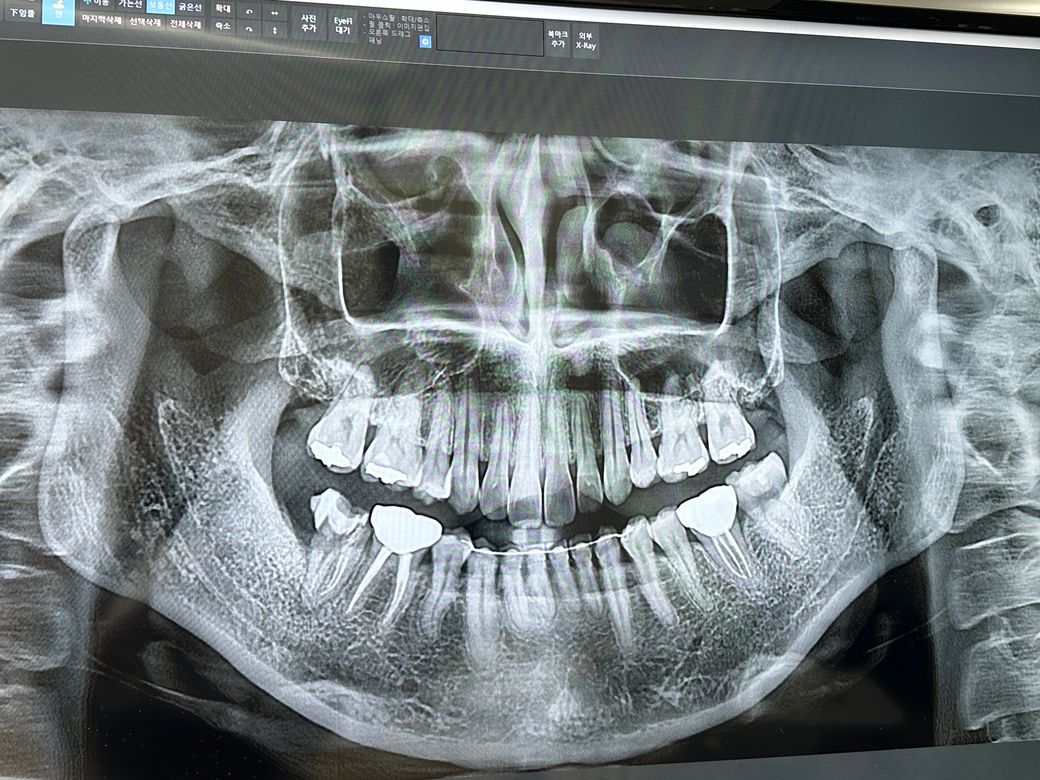

임플란트하려고 하는데ㅠㅠ 상담문의드립니다

오른쪽 아래 맨끝 어금니가 충치로 인해 발치 권유 받았습니다

해당 부분의 경우에는 발치와보존술 보다는 발치 이후 염증이 어느정도 회복된 이후에 임플란트를 식립하는 것이 좋아 보입니다. 다만 정상적인 교합을 위해서 대합치를 삭제하는 것이 필요해보이며 이는 임상적인 사진 등이 필요합니다. 대합치가 너무 내려왔다면 크라운을 해야할 수도 있어 보입니다.

저정도 상태라면 뼈이식을 하지 않고 기다렷다 하셔도 충분할것같습니다. 대합치는 추후 치아가 정출되면 보철물을 다시 하셔야될것같습니다.